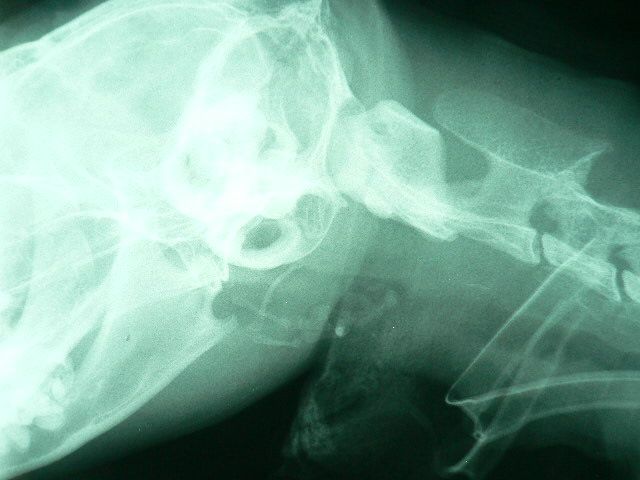

慢性腎不全の投薬、栄養補給のために、食道チューブを入れて順調な経過をたどっていたミー子でしたが、最近、食事をチューブから入れる時に嘔吐があるという訴えがありました。レントゲン写真を撮ると喉に白い塊がみえるではありませんか!

●喉周囲の石灰沈着???

喉に白く見えるものが分かりますか?石灰(カルシウム)あるいは膿と思われる物が沈着して、喉の周囲を圧迫しているのが見えます。最近、吐き気があるとの訴えは、慢性腎不全の影響ではなく、これが原因だったようです。表面の粘膜をレーザーで切開し、沈着物を摘出および掻き出すことにしました。

再び喉のレントゲン撮影を行いました。最初のレントゲンと比較すると良くなっているのが分かりますが、白い沈着物が消失しています。